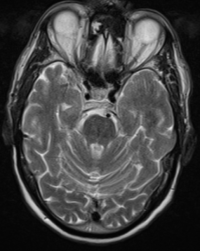

Series 001 — Frontal Lobe Mass (Likely Meningioma) Overview

Initial scan set with key anatomical landmarks and first-pass observations.